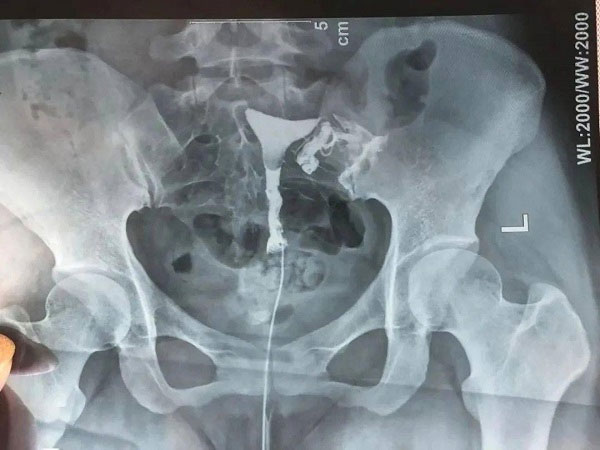

导丝介入疏通输卵管也被称之为输卵管阻塞再通术,主要就是在影响设备的全程引导下,通过女性的阴道达到子宫然后到达输卵管,找到不通畅的输卵管,就能够明确输卵管出现病变的原因,然后就可以达到诊断和治疗的双重目的。这种介入治疗的过程是比较简单的,并且时间也比较短,一般10分钟就可以疏通输卵管,疏通率可以达到90%,患者可以了解一下。

导丝介入疏通输卵管过程

3.导丝介入:将宫腔镜推进女性的宫底,然后找到输卵管的位置,将导管在宫腔镜的引导下插入女性的输卵管,然后想输卵管中注入药物查看情况;

4.疏通:注入药物后如果就需要将导丝送入输卵管中然后进行通液,直到输卵管不再出现反流现象即可。